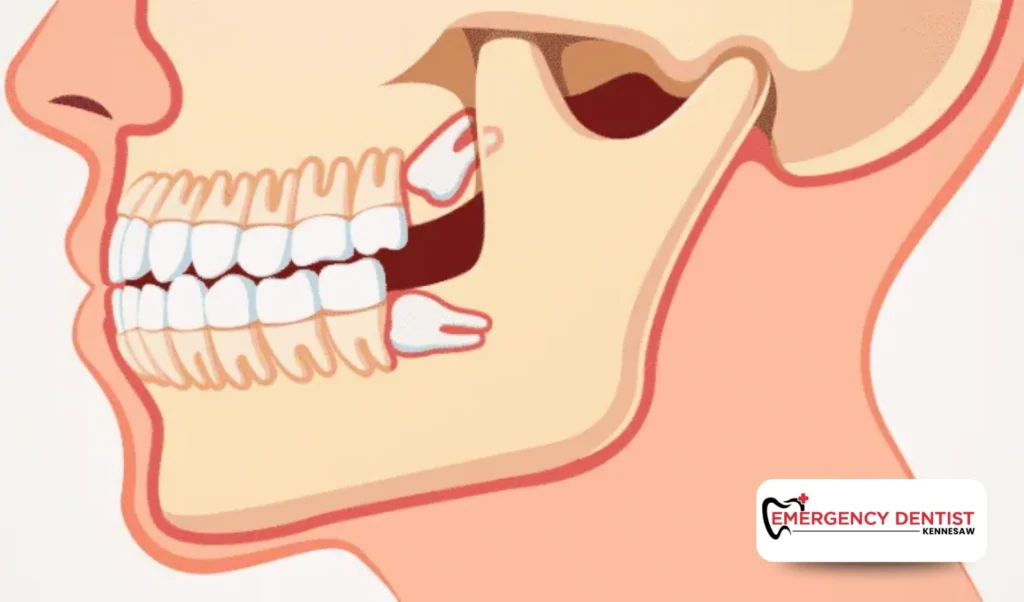

An impacted wisdom tooth does not fully emerge through the gums. It may grow at an angle or press against other teeth. These situations often require oral surgery techniques.

Because more time and planning are involved, impacted cases tend to increase the average cost of a wisdom tooth removal. When people ask, how much is a wisdom tooth extraction, the answer often depends on whether the tooth is impacted or fully erupted.